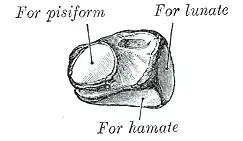

Le triquétrum a une forme globale pyramidale à sommet antéro-interne. Il est situé médialement au lunatum.

- une face inféro-interne possédant une facette ovalaire concave s'articulant avec le pisiforme pour former l'articulation de l'os pisiforme.

- une face latérale triangulaire articulaire avec le lunatum,

- une face inférieure triangulaire et concave qui s'articule avec l'hamatum,